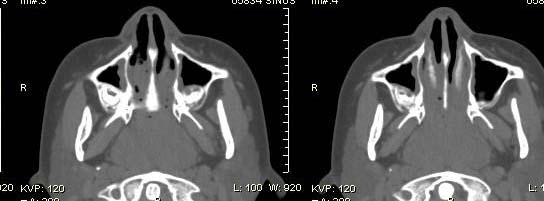

以下是引用随光逐影在2009-6-4 21:13:00的发言:[br]1)考虑鼻咽腺样体重度肥大。2)双侧鼻腔炎性改变。3)双侧上颌窦、双侧筛窦及左侧蝶窦炎症。

以下是引用zsl6918在2009-6-5 7:42:00的发言:[br]首先考虑鼻咽腺样体重度肥大,鉴别纤维血管瘤.强化有助明确.